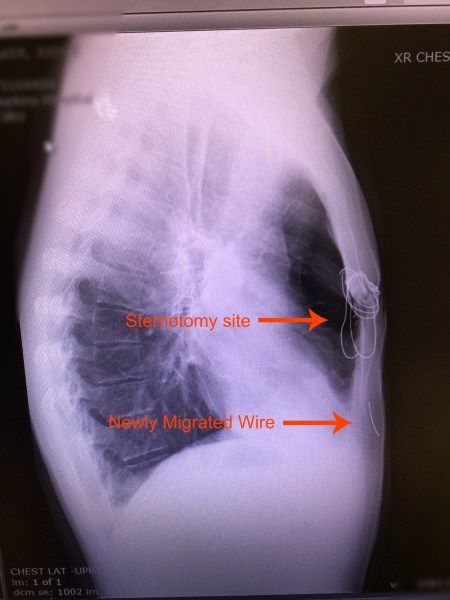

The list could go on and on. He’s had numerous ER visits and surgeries/procedures since his transplant. Remember the broken sternal wires he had to have removed? The bronchoscopy that caused a collapsed lung and need for chest tube and hospitalization? We know another surgery to remove more kidney stones is in his future. Despite all these things, Jody would say post transplant life is pretty good. If you’ve followed Jody’s story you know he’s not a complainer. He accepts his “issues” and doesn’t let them stop him; they pale in comparison to the issues his old CF lungs caused him.